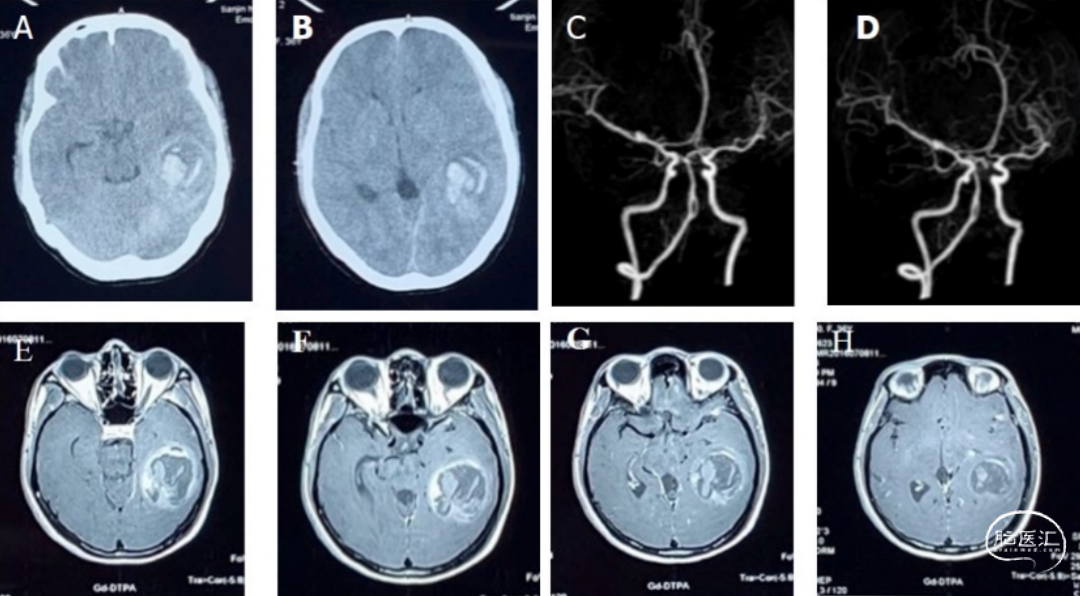

- 患者第1次急诊来院,在就诊过程中,突发神志不清,遂紧急行头CT平扫,提示左颞出血性病变(图1A-B)

- 为进行鉴别诊断,行头CTA,以除外脑血管畸形引起的出血(图1C-D)。同时,行头MRI增强(图1E-H),结合影像学特点,考虑肿瘤卒中,高级别脑胶质瘤可能性大

图1.首次术前影像评估(2016-07-08)。A-B:头CT平扫;C-D:头CTA;E-H:头MRI增强